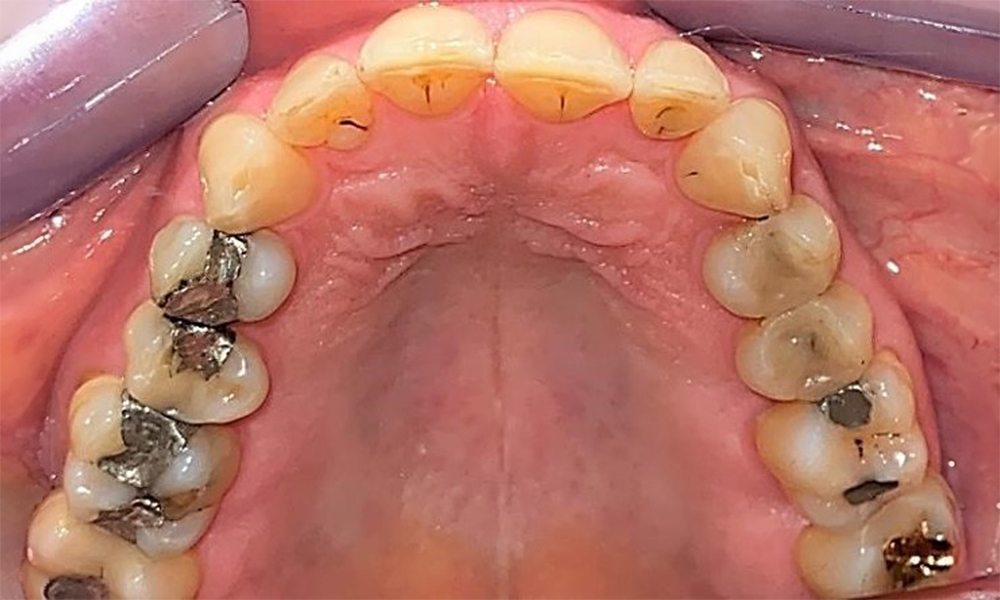

Occlusal view of the maxilla. Insufficient amalgam filling of 14 with a marginal gap.

Fig. 5 Occlusal view of the maxilla. Insufficient amalgam filling of 14 with a marginal gap. © Dr R. Krapf

Dental findings

The patient has a full dentition with 28 teeth, which includes amalgam and composite fillings in the molar and premolar regions. There is a visible clinical marginal gap present on tooth 14. Tooth 27 has an adequate gold inlay. There are also generalized attritions and abrasions. (Fig. 2, Fig. 3, Fig. 4, Fig. 5, Fig. 6)